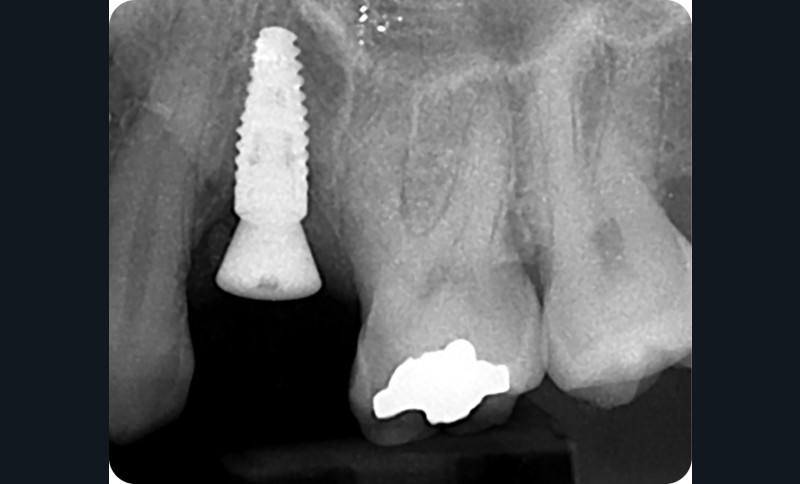

Les critères de succès de l’ostéointégration sont définis depuis des décennies (immobilité de l’implant, pas de radio transparence autour de l’implant ni de douleur, perte osseuse limitée et possibilité d’y assembler une prothèse) [1, 2] (fig. 1 et 2). à ces critères cliniques et radiologiques s’ajoutent des critères esthétiques, avec, dans le secteur antérieur, le Pink Esthetic Score (PES) par exemple [3]. Le PES est un outil pour quantifier et comparer les réhabilitations implantaires. Une de ses composantes majeures est la présence et la santé des tissus mous péri-implantaires, mais aussi la ligne d’émergence de la prothèse supra-implantaire. Cette ligne et la santé des tissus mous sont directement liées au profil d’émergence de la restauration, zone transmuqueuse de la prothèse qui est prépondérante à bien des égards : nous allons le détailler ci-après.

Sur une dent naturelle, le profil d’émergence est la zone de transition entre la racine et la couronne dentaire. En prothèse implantaire, le profil d’émergence se définit comme le contour des éléments prothétiques personnalisés et adaptés à l’architecture gingivale péri-implantaire (fig. 3). Le problème est que les racines dentaires, à la différence des implants qui les remplacent, ne sont pas de section ronde [5]. Les différentes vis de cicatrisation ne permettent pas d’obtenir un profil d’émergence proche de la réalité.